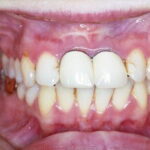

Hyalinosis Cutis et Mucosae=تنكس هياليني جلدي ومخاطي